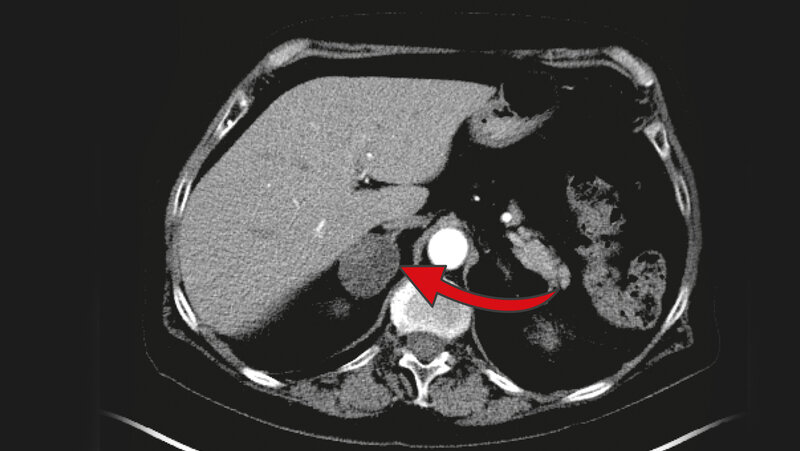

Drei Zentimeter großer Nebennierentumor

Das MRT zeigt einen drei Zentimeter großen Nebennierentumor auf der rechten Seite. 80 bis 90 Prozent dieser Tumore, die meist zufällig entdeckt werden, sind gutartig. UKW

Nebennierentumoren gehören laut Deutscher Gesellschaft für Endokrinologie zu den häufigsten Tumoren beim Menschen überhaupt. Drei Prozent der über 50-Jährigen haben Nebennierentumore. Bei den über 80-Jährigen ist sogar jeder zehnte betroffen. 80 bis 90 Prozent dieser Tumore, die meist zufällig, zum Beispiel bei einer Computertomografie bei Gallenproblemen, Nierensteinen oder Rückenleiden, entdeckt werden, sind jedoch gutartig und vermeintlich harmlos. Vermeintlich deshalb, weil eine leicht gesteigerte Produktion des Hormons Kortisol, die viele dieser Tumore mit sich bringen, vor einiger Zeit die Meinungen spaltete: Muss man den Tumor operativ entfernen oder nicht?